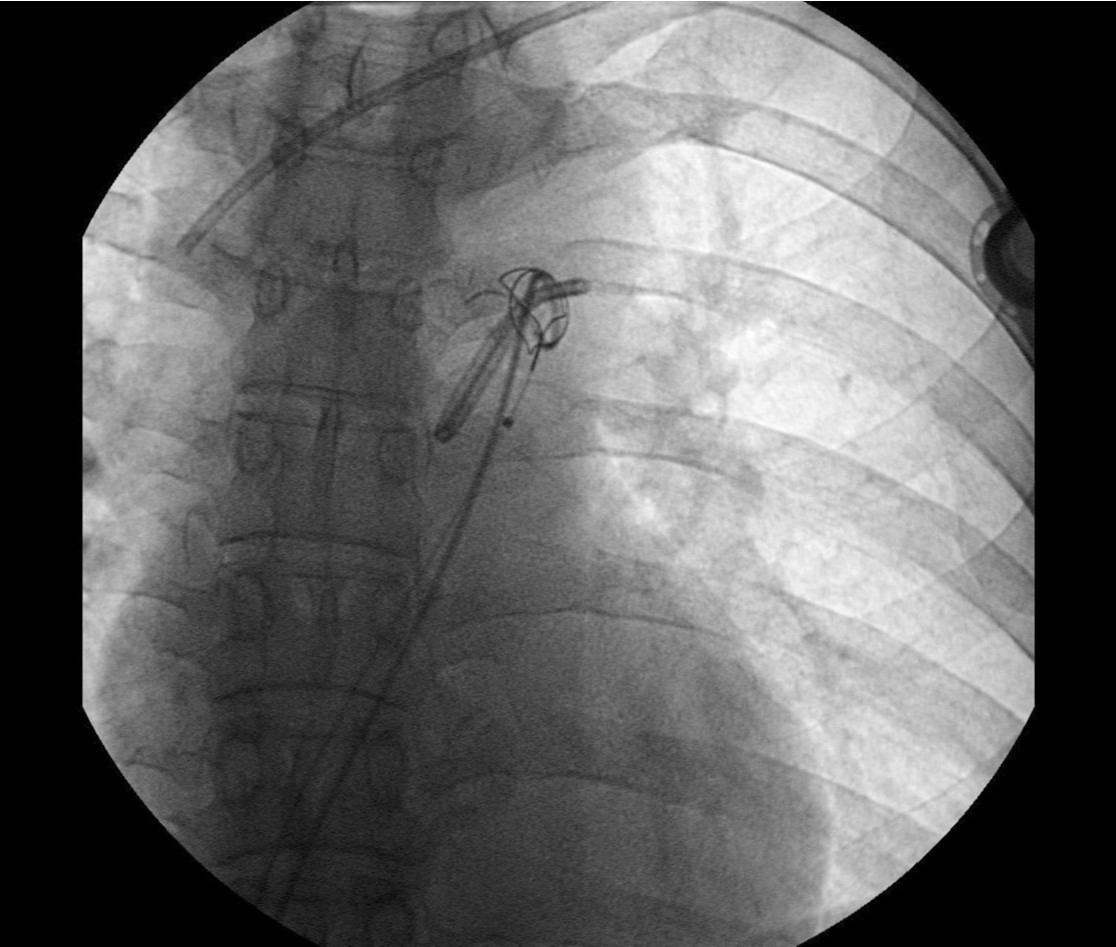

Fig. 4. D

(D) Removed chemoport tube.